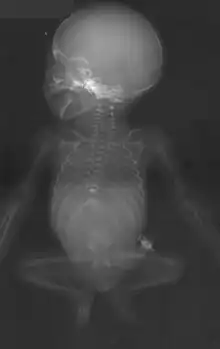

Caudal regression syndrome, or sacral agenesis (or hypoplasia of the sacrum), is a rare birth defect. It is a congenital disorder in which the fetal development of the lower spine—the caudal partition of the spine—is abnormal.[1] It occurs at a rate of approximately one per 60,000 live births.[2]

This condition exists in a variety of forms, ranging from partial absence of the tail bone regions of the spine to absence of the lower vertebrae, pelvis and parts of the thoracic and/or lumbar areas of the spine. In some cases, where only a small part of the spine is absent, there may be no outward sign of the condition. In cases where more substantial areas of the spine are absent, there may be fused, webbed or smaller lower extremities and paralysis. Bowel and bladder control is usually affected.